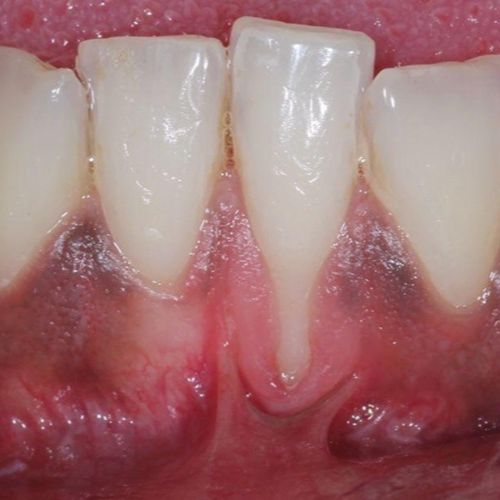

| Untreated severe gum disease | Gum disease treated and stabilised by Dr Halai |